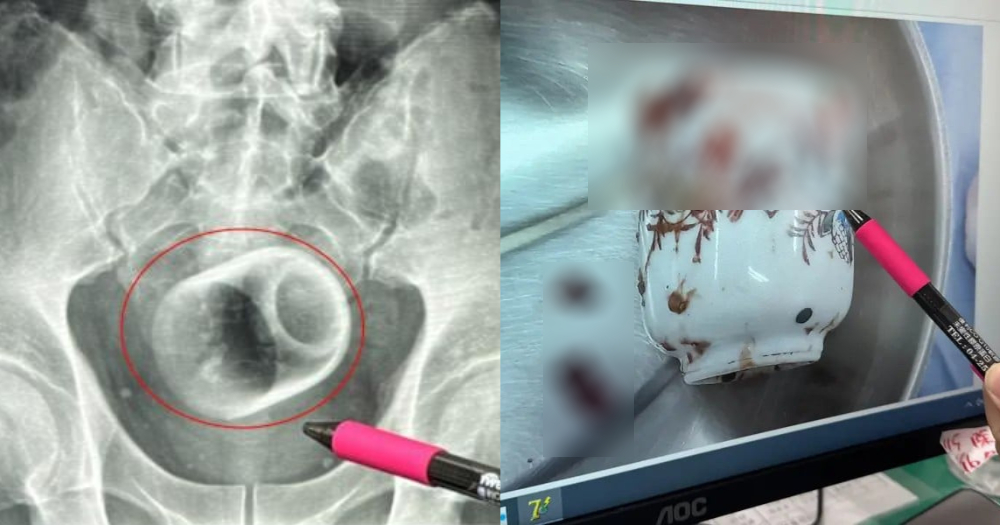

schizoidman@lemmy.zip to Not The Onion@lemmy.worldEnglish · 3 months agoMan in Taiwan somehow gets 8cm by 6cm ceramic cup in bottom, claims it got there 'by accident'mothership.sgexternal-linkmessage-square49linkfedilinkarrow-up1224arrow-down18

arrow-up1216arrow-down1external-linkMan in Taiwan somehow gets 8cm by 6cm ceramic cup in bottom, claims it got there 'by accident'mothership.sgschizoidman@lemmy.zip to Not The Onion@lemmy.worldEnglish · 3 months agomessage-square49linkfedilink